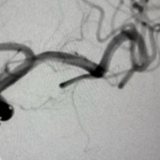

血泡样动脉瘤栓塞前后对比。

面对高风险挑战,脑病科介入团队沉着应对,术前反复推演手术路径、制定个体化“支架辅助弹簧圈栓塞”方案;术中精准操控微导管,在瘤体内精细填塞弹簧圈并植入支架重塑载瘤动脉。术后造影显示,动脉瘤完全闭塞、载瘤动脉血流通畅,患者术后恢复良好,已脱离生命危险。其余3例常规动脉瘤患者,均通过微创股动脉穿刺完成栓塞,无需开颅、创伤极小,大幅缩短住院周期。